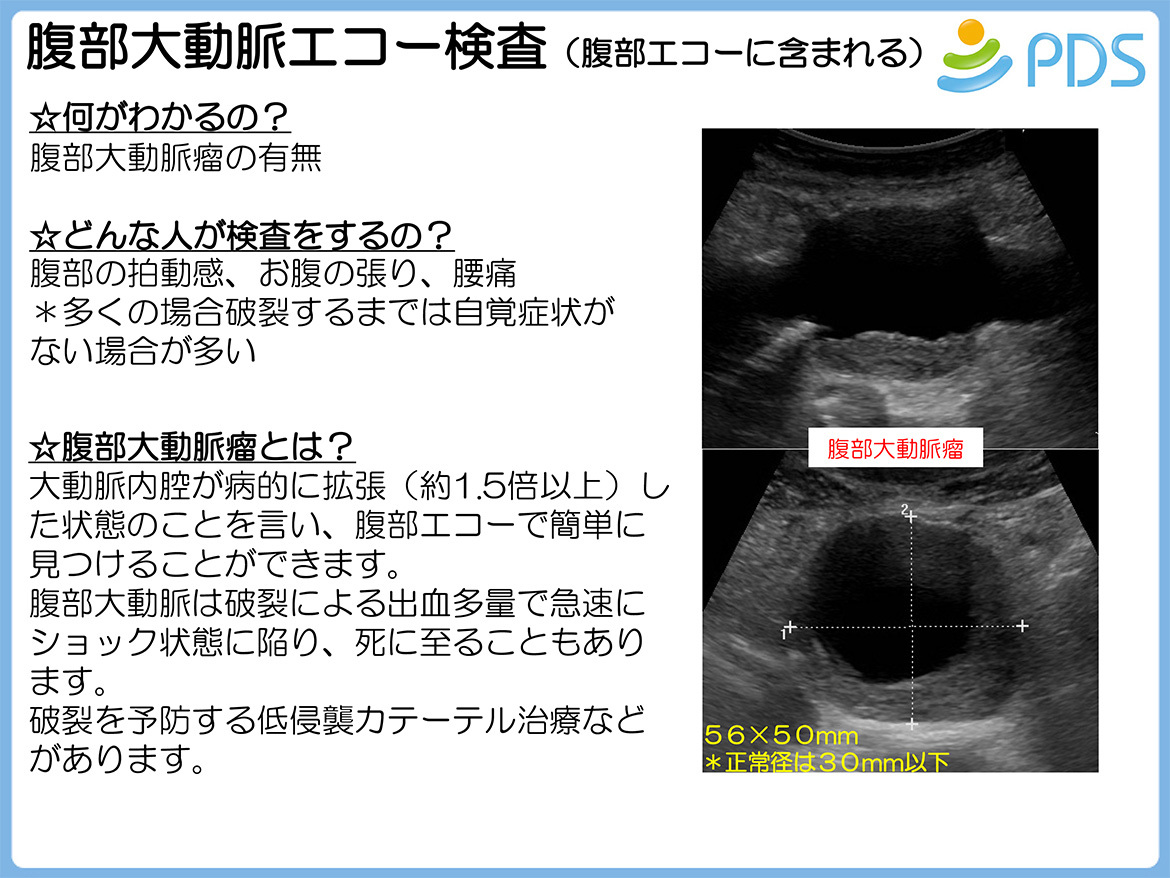

○ 超音波診断装置(カラー) (持田シーメンスメディカル, 超音波検査 | これまさクリニック 府中市是政 是政駅 内科 消化,

超音波検査 | これまさクリニック 府中市是政 是政駅 内科 消化,![超音波診断装置|GEヘルスケア|PRODUCT_CODE]|中古医療機器の 超音波診断装置|GEヘルスケア|PRODUCT_CODE]|中古医療機器の](https://www.quon-healthcare.com/contents/lot/2/10_0000013313_2_0_cLNIqh.jpg) 超音波診断装置|GEヘルスケア|PRODUCT_CODE]|中古医療機器の,